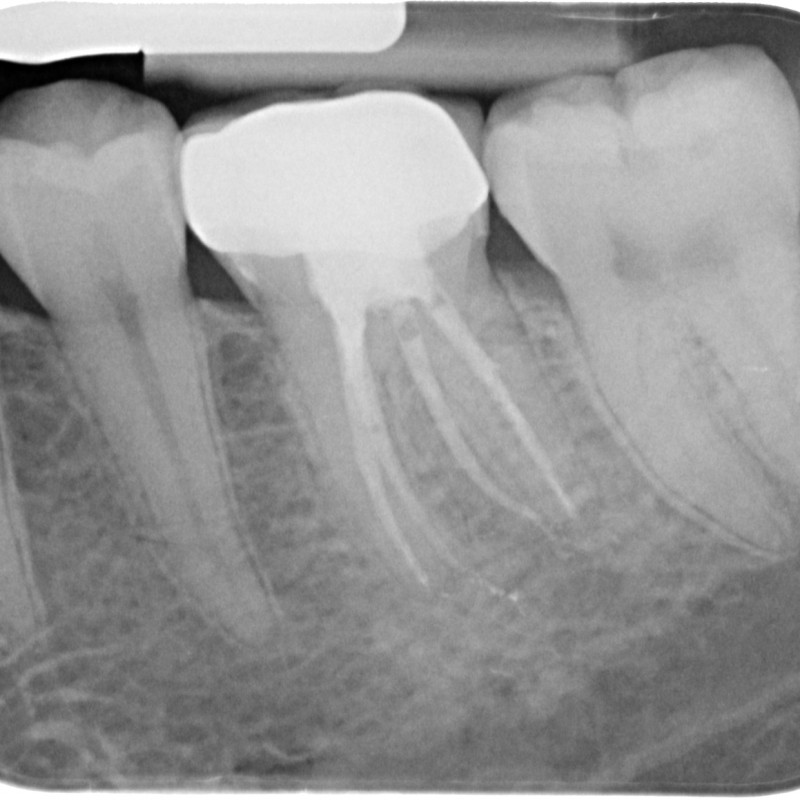

501013-08-6049-X-20150508-122214-XPZQKLSCU9AB-4